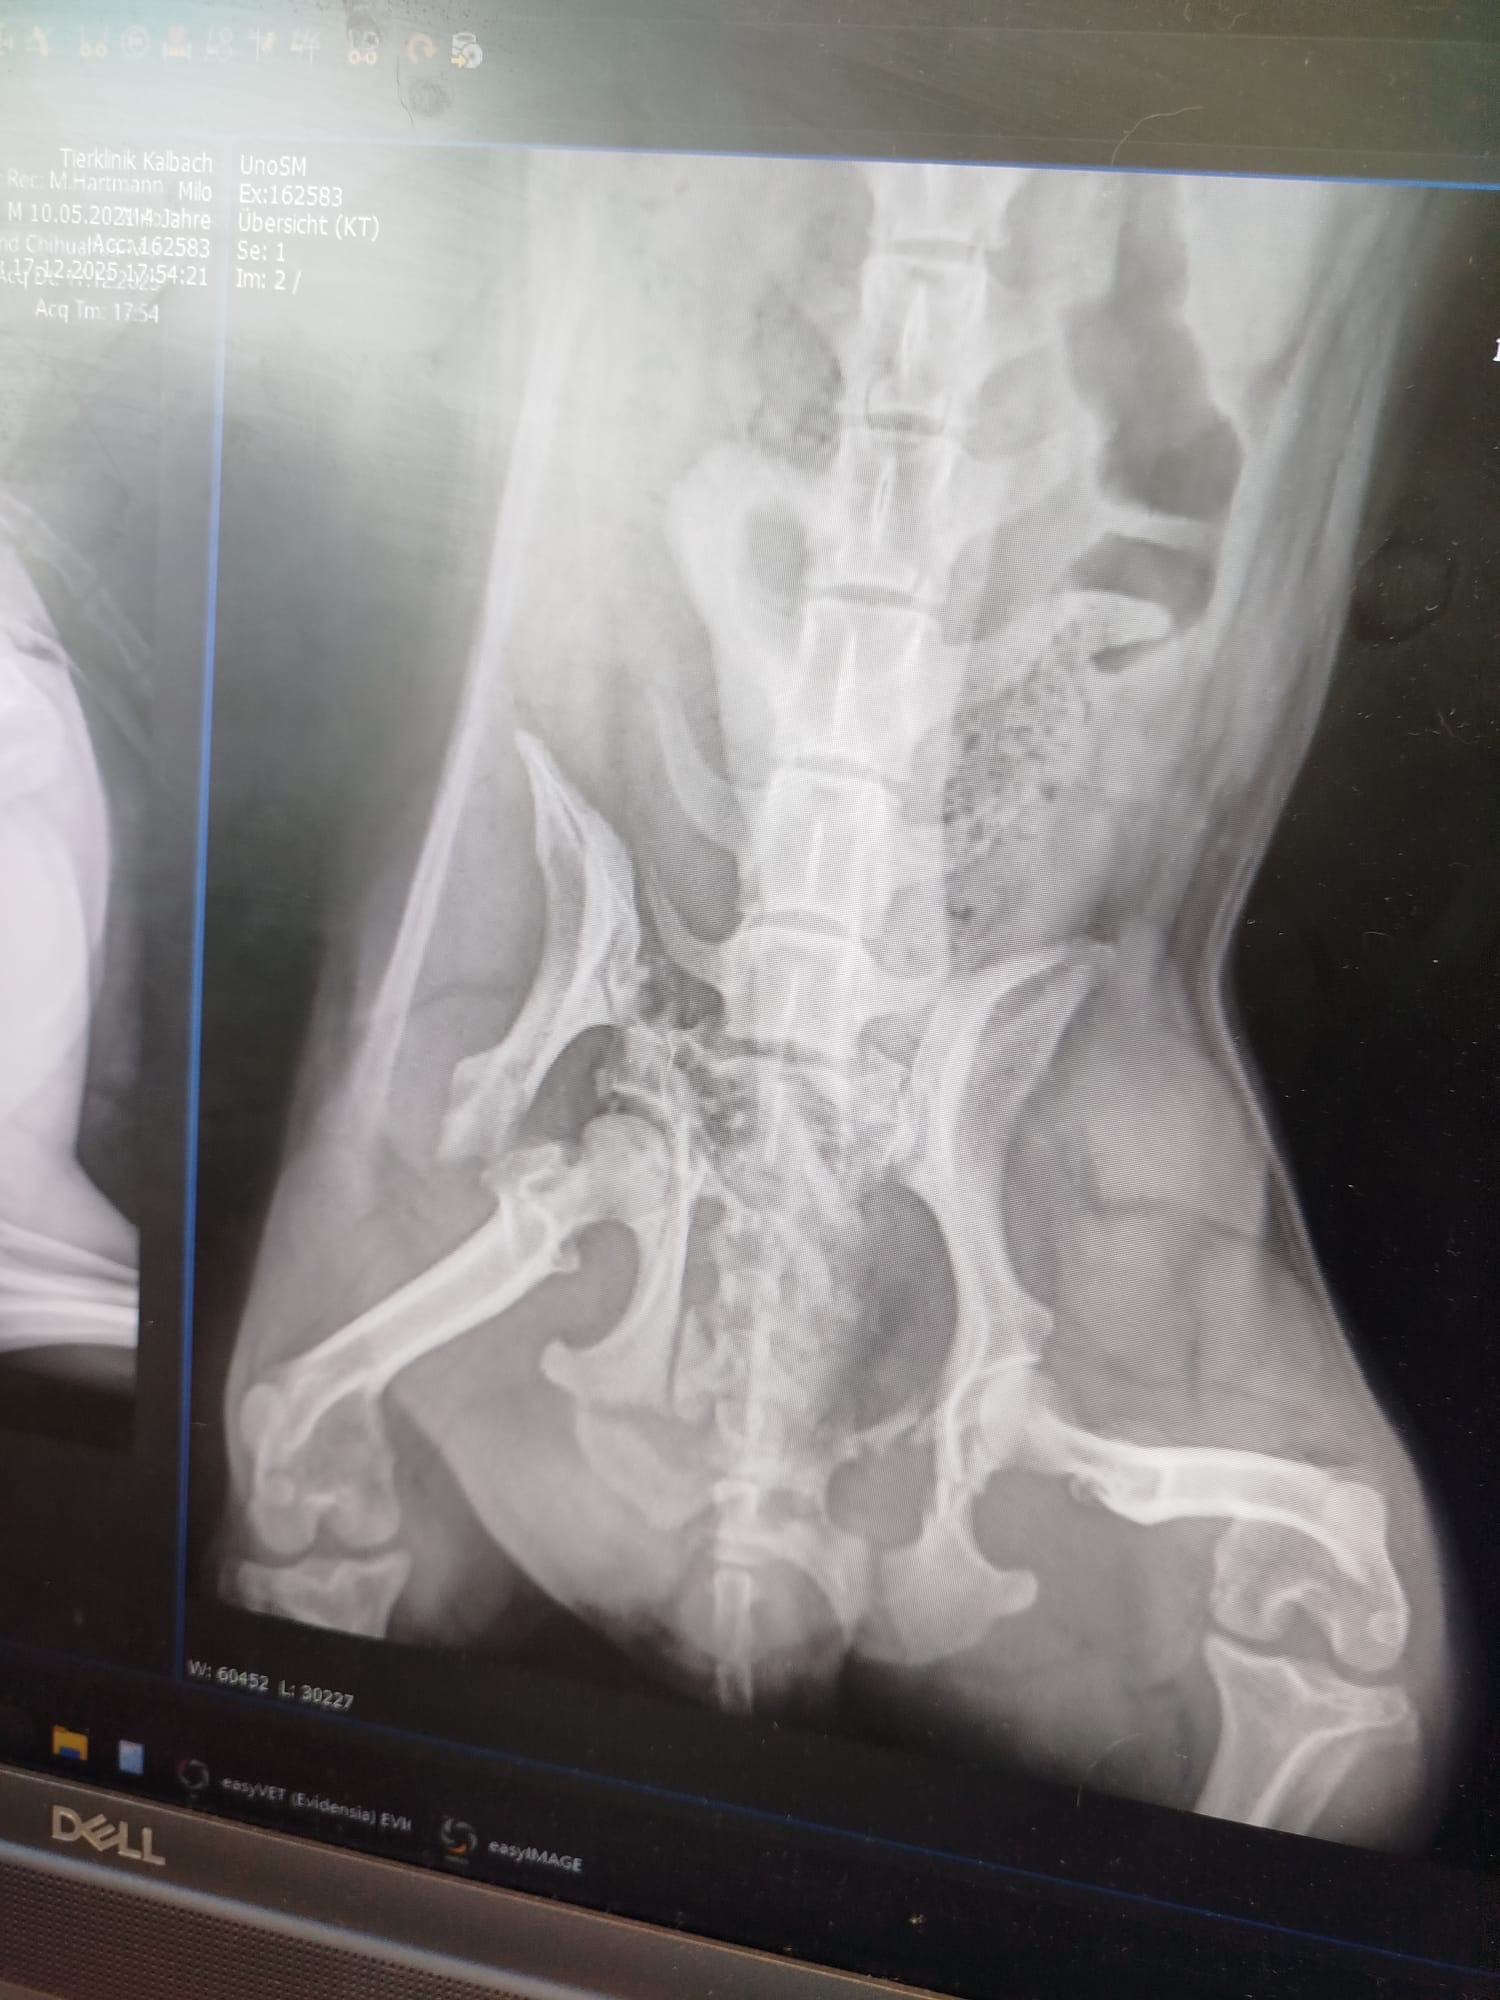

Hallo ich bin Madleine ich möchte euch bitten uns zu helfen der Hund meiner Cousine Jane und Cousin Aiden wurde gestern leider angefahren er muss operiert werden da er eine dreifache Beckenfraktur hat leider können wir die hohen op kosten nicht alleine stemmen deshalb bitten wir mit diesen aufruf um eure unterstützung wir bedanken uns herzlich im voraus für eure hilfe